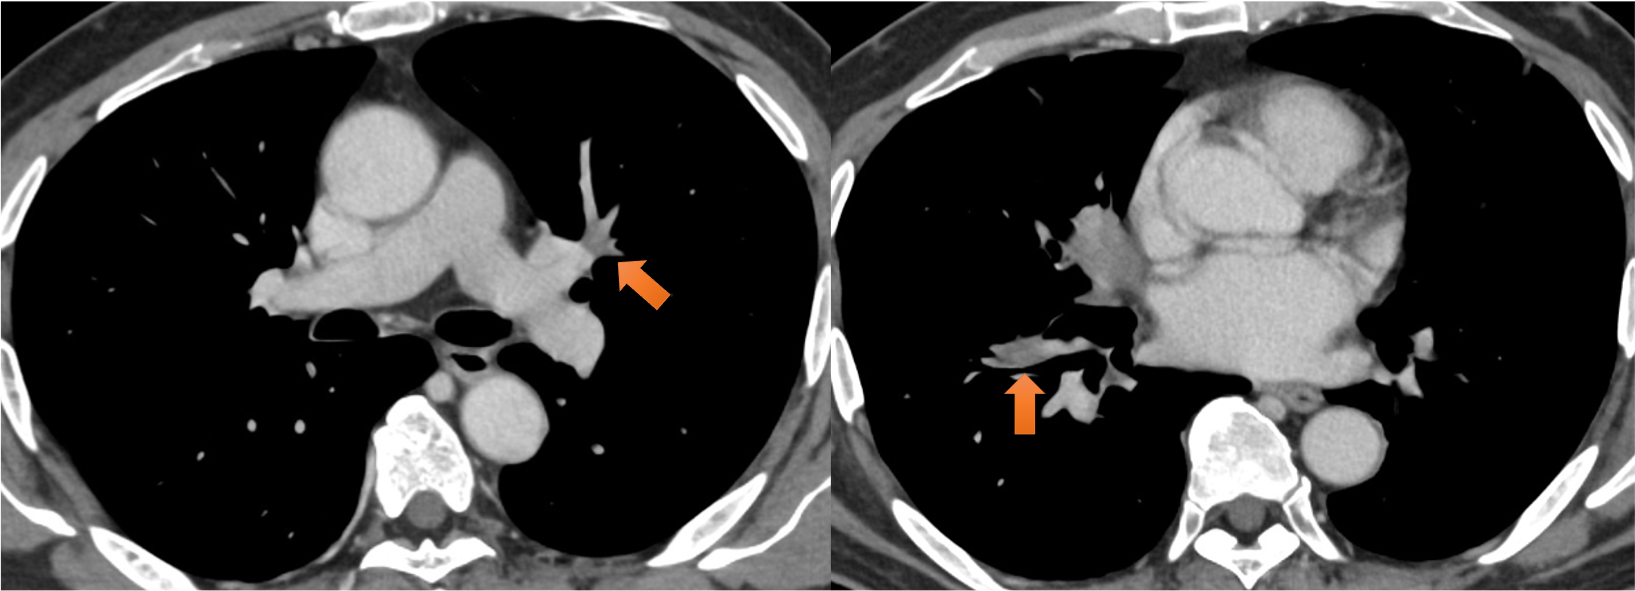

図6.肺動脈造影欠損像

右肺下葉動脈(A8)、左肺上下葉動脈(A3やA8、A9など)に造影欠損あり、造影で一部、増強効果を伴っており、腫瘍塞栓/血栓が疑われた。

図7.肺静脈造影欠損像

右下葉肺静脈壁に沿うように造影欠損あり、腫瘍進展が疑われた。化学療法後、消失が確認された。